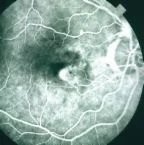

Types of Macular Degeneration

- Wet type: RPE detachment and choroidal neovascularization

- Fluorescein angiography

- Choroidal neovascularization